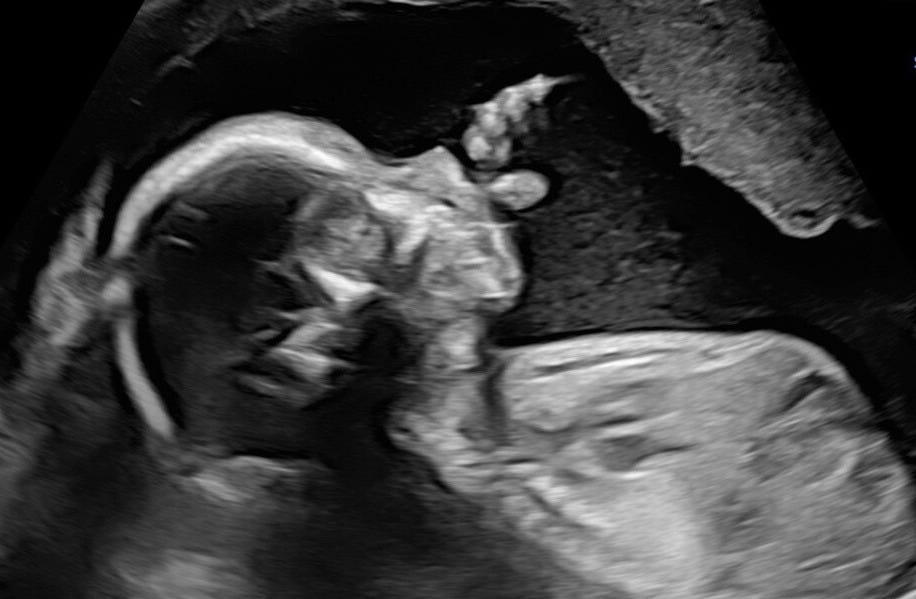

And yet, I wrote my last newsletter in February and subsequently went into a five-month-long creative freeze. I’m not going to beat around the bush: I got pregnant.

In January, I went to a clinic in Copenhagen and did my fourth insemination with donor sperm (the first three attempts having been unsuccessful). At the beginning of February, I found out I was pregnant. I am now in my eighth month, which is incredible.